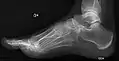

قدم جوفاء[1] أو قدم خمصية[1] (بالإنجليزية: Pes cavus) وتُعرف أيضًا باسم قوس عالية (بالإنجليزية: high arch) هو نوعٌ من القدم البشرية، حيثُ يكون فيه أخمص القدم مجوفًا بوضوح عند تحميل وزنٍ عليه، أي أنَّ هُناك ثنيٌ أخمصي ثابت في القدم. تُعتبر القدم الجوفاء عكس القدم المسطحة والتي تحدث بشكلٍ أقل شيوعًا.

![]() قوس عالية في قدم شخص مُصاب باعتلالٍ عصبي وراثي قوس عالية في قدم شخص مُصاب باعتلالٍ عصبي وراثي | |